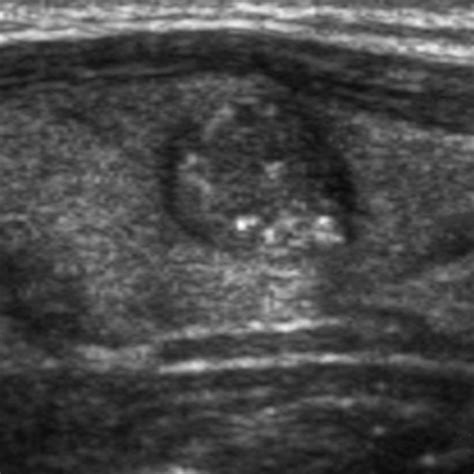

Pattern Recognition of Benign and Malignant Thyroid Nodules Ultrasound